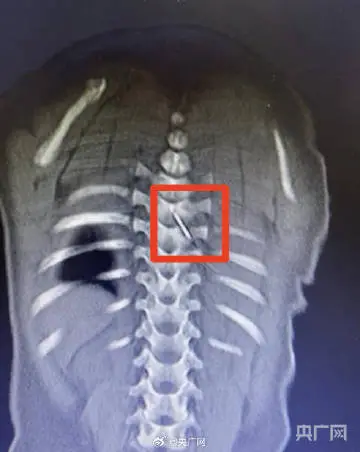

9月大男婴被被子里的缝衣针扎进脊柱

近日,合肥一名9个月大男婴睡觉时,裹在被中的一根3厘米缝衣针扎入其背部,并随移动刺入脊柱,紧贴脊髓。经安徽省儿童医院多学科团队连夜手术,在显微镜下精准取出,未伤及神经。孩子已康复出院。医生紧急提醒:务必收好针等尖锐物品,类似刺伤切勿自行拔除!